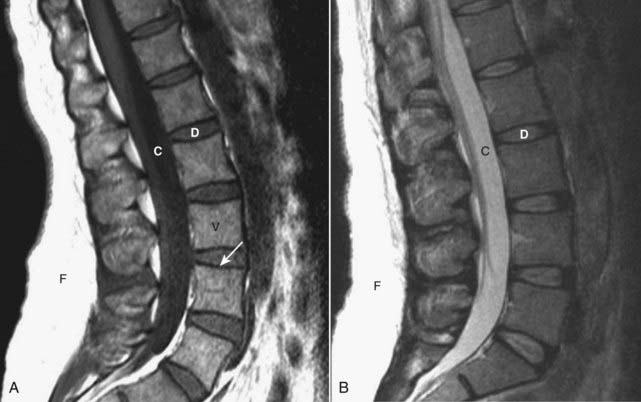

imageOn T1-weighted sagittal MRI images of the spine, the vertebral bodies, containing bone marrow, will normally be of high signal intensity (bright), the disks will be lower in signal intensity, and CSF in the thecal sac will have a low signal intensity (dark) (Fig. 24-4A).

image

Figure 24-4 Normal MRI lumbar spine, T1-weighted and T2-weighted images.

A, Sagittal T1-weighted image demonstrates the normal dark appearance of the disks (D) relative to the vertebral body (V). The CSF in the spinal canal is dark (C), and the subcutaneous fat of the back is bright (F). Cortical bone has a low signal (solid white arrow). B, Sagittal T2-weighted image demonstrates the normal appearance of the disks (D), which are slightly higher intensity (brighter) than the vertebral bodies. The CSF (C) in the spinal canal is now bright, and the subcutaneous fat (F) of the back remains bright.

image On conventional T2-weighted images, the vertebral body will be slightly lower in signal intensity than the disks, while the CSF will appear bright (the reverse of T1) (Fig. 24-4B).

image Cortical bone is dark (has a low signal) on all sequences.